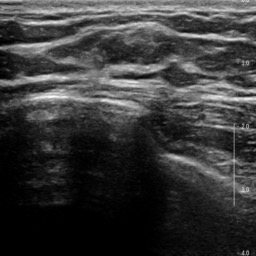

Ultrasonography is an important routine examination for breast cancer diagnosis, due to its non-invasive, radiation-free and low-cost properties. However, it is still not the first-line screening test for breast cancer due to its inherent limitations. It would be a tremendous success if we can precisely diagnose breast cancer by breast ultrasound images (BUS). Many learning-based computer-aided diagnostic methods have been proposed to achieve breast cancer diagnosis/lesion classification. However, most of them require a pre-define ROI and then classify the lesion inside the ROI. Conventional classification backbones, such as VGG16 and ResNet50, can achieve promising classification results with no ROI requirement. But these models lack interpretability, thus restricting their use in clinical practice. In this study, we propose a novel ROI-free model for breast cancer diagnosis in ultrasound images with interpretable feature representations. We leverage the anatomical prior knowledge that malignant and benign tumors have different spatial relationships between different tissue layers, and propose a HoVer-Transformer to formulate this prior knowledge. The proposed HoVer-Trans block extracts the inter- and intra-layer spatial information horizontally and vertically. We conduct and release an open dataset GDPH&GYFYY for breast cancer diagnosis in BUS. The proposed model is evaluated in three datasets by comparing with four CNN-based models and two vision transformer models via a five-fold cross validation. It achieves state-of-the-art classification performance with the best model interpretability.

翻译:超声波分析是乳腺癌诊断的一个重要常规检查,原因是其非侵入性、无辐射和低成本的特性。然而,由于其内在局限性,它仍不是乳腺癌的第一线筛选测试。如果我们能够精确地通过乳房超声图像诊断乳腺癌(BUS),它将是一个巨大的成功。我们提出了许多基于学习的计算机辅助诊断方法,以实现乳腺癌诊断/感官分类。然而,其中多数方法需要事先确定性能模型,然后对ROI内部的跨值进行分类。常规分类支柱,如VGG16和ResNet50等,可以在没有ROI要求的情况下实现有希望的分类结果。但是这些模型缺乏可解释性,从而限制了其在临床实践中的使用。在本研究中,我们提出了一个新的无乳腺癌诊断模型,在超声波图像中进行解释性特征描述。我们利用了先前的解剖学学学知识,即恶性肿瘤和良性肿瘤模型在不同组织层之间有着不同的空间关系,并提议采用状态解析法来编制这一先前的知识。拟议中的HOVer-Trans-Trading-Tradef-trainal Ex-deal-dealal-deal-deal-deal-degraphal-deal-deal-deal-deal-deal-deal disal disal-dal-dal-dal-dal-dal-deal-deal-dal-deal-deal-deal-dal-dal-dal-dal-dal-dal-dal-dal-dal-dal-dal-dal-dal-dal-I-dal-Iversal-dal-Ial-d-d-I-d-d-I-I-I-I-I-I-I-I-I-I-I-I-I-I-I-I-I-I-I-I-I-I-I-I-I-Ial-I-Ial-Ial-I-I-I-I-I-I-I-I-I-I-I-I-I-I-I-I-I-I-I-I-I-I-I-I-I-I-I-I-I-I-I-I-